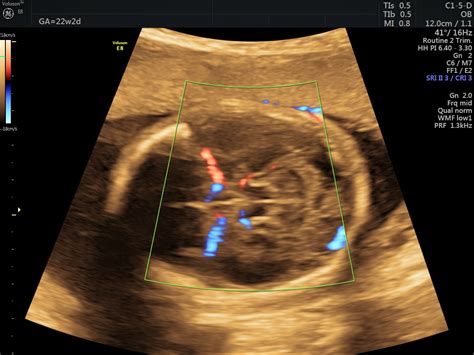

La finalul lunii a noua, bebelușul tău atinge dimensiunea unui pepene dulce. Cu fiecare zi ce trece, micuțul se pregătește pentru debutul în lumea exterioară, iar tu vei simți fiecare mișcare și bătăi de inimă. În luna a noua, bebelușul dobândește toate reflexele esențiale, inclusiv reflexul de supt, Moro, de a apuca și de înghițire. Aceste abilități îl vor ajuta să se adapteze rapid la mediul extern după naștere. După săptămâna 37, bebelușul este considerat la termen. Este gata să vină pe lume, dar rămâi pregătită pentru orice surpriză și să ai totul pregătit pentru sosirea lui. În această fază, bebelușul primește anticorpi de la mamă, pregătindu-l pentru a lupta împotriva infecțiilor imediat după naștere. Este un dar valoros pe care îl primește pentru a-și întări sistemul imunitar.

În această perioadă, bebelușul poate să-și reducă activitatea, dar vei simți mișcările lui zilnic. Este momentul perfect să te conectezi emoțional cu micuțul și să te pregătești pentru marea întâlnire. Cu toate acestea, dacă observi o reducere semnificativă a mișcărilor fetale, este recomandat să te adresezi medicului pentru monitorizare. Lipsa mișcărilor poate fi și un semn că bebelușul este în perioada de somn profund, dar este important să te asiguri că totul este în regulă.